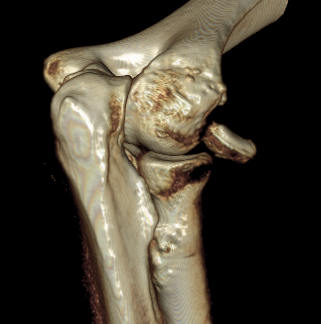

Terrible Triad

Definition

Elbow dislocation with radial head fracture + coronoid fracture + MCL tear